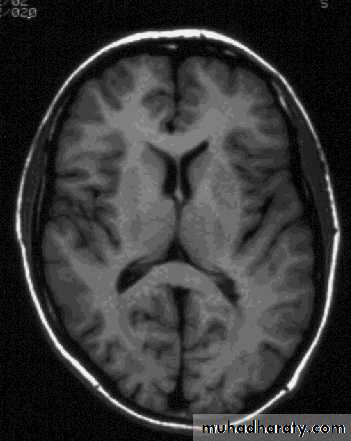

ComparisonsMRI image

CAT image

head

Compare bone and soft tissue density